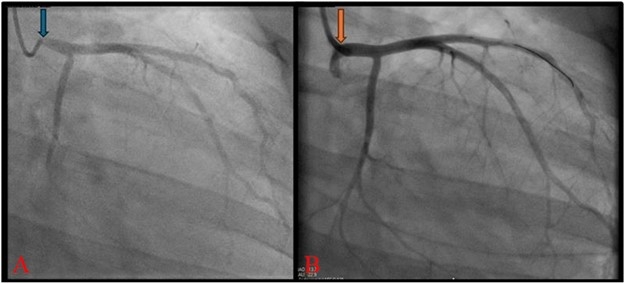

A healthy 42-year-old woman with a BRCA mutation presented for breast cancer screening via a magnetic resonance imaging (MRI). This revealed cardiomegaly, for which she was referred to our hospital for workup. Her exam revealed a widened pulse pressure (70 mmHg) and a diastolic murmur at the right upper sternal border. Subsequently, a computed tomography (CT) and transthoracic echocardiogram showed perivascular fat-stranding concerning for aortitis (Figure 1A) and aortic regurgitation (AR) with left ventricular (LV) dilation and dysfunction, respectively. These findings were confirmed with a cardiac MRI (Figure 2) and transesophageal echo. Subsequent coronary CT angiogram ruled out aortic dissection but revealed 70% ostial left main (LM) coronary artery stenosis (Figure 1B), which was confirmed on coronary angiogram (Figure 3A).

However, her course was complicated by refractory chest pain requiring nitroglycerin infusion. After extensive discussions, via shared decision-making we proceeded with a temporizing, high-risk coronary stenting as a bridge to surgery following successful tapering of immunosuppressive therapy. She underwent a successful PCI (Figure 3B) and was initiated on dual-antiplatelet therapy. Ultimately, she was discharged on a prednisone taper and methotrexate, with plans for interval SAVR and CABG once on the lowest dose steroid.